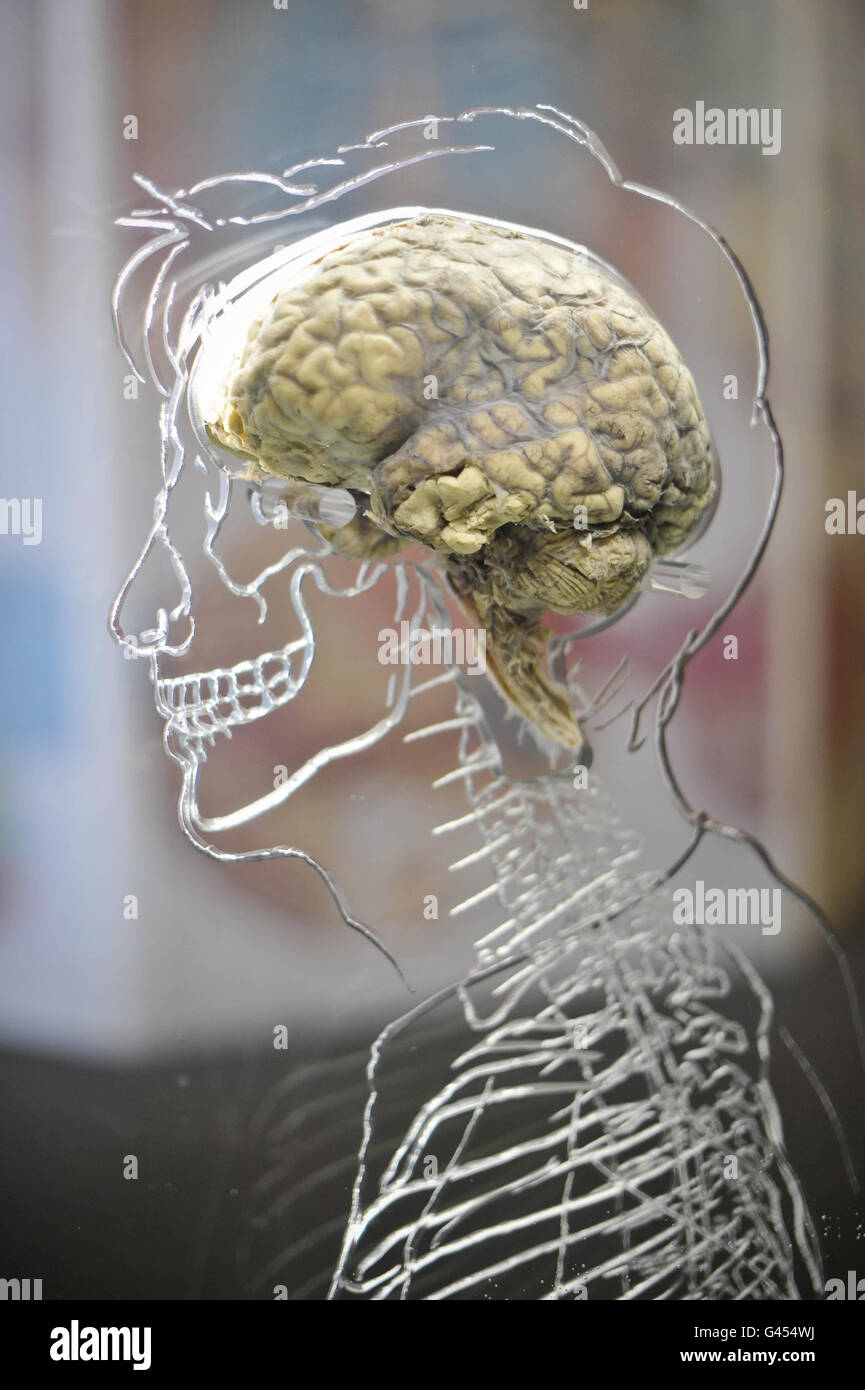

Ein echtes menschliches Gehirn in Flüssigkeit mit einem maßstabsgefertigten Skelett, zentralem Nervensystem und menschlicher Silhouette in Acryl gehauen, in der @Bristol Science Attraction als Teil der neuen Ausstellung "All About US", die am Freitag, 11. März, für die Öffentlichkeit geöffnet wird. Stockfotohttps://www.alamy.de/image-license-details/?v=1https://www.alamy.de/stockfoto-ein-echtes-menschliches-gehirn-in-flussigkeit-mit-einem-massstabsgefertigten-skelett-zentralem-nervensystem-und-menschlicher-silhouette-in-acryl-gehauen-in-der-@bristol-science-attraction-als-teil-der-neuen-ausstellung-all-about-us-die-am-freitag-11-marz-fur-die-offentlichkeit-geoffnet-wird-105834225.html

Ein echtes menschliches Gehirn in Flüssigkeit mit einem maßstabsgefertigten Skelett, zentralem Nervensystem und menschlicher Silhouette in Acryl gehauen, in der @Bristol Science Attraction als Teil der neuen Ausstellung "All About US", die am Freitag, 11. März, für die Öffentlichkeit geöffnet wird. Stockfotohttps://www.alamy.de/image-license-details/?v=1https://www.alamy.de/stockfoto-ein-echtes-menschliches-gehirn-in-flussigkeit-mit-einem-massstabsgefertigten-skelett-zentralem-nervensystem-und-menschlicher-silhouette-in-acryl-gehauen-in-der-@bristol-science-attraction-als-teil-der-neuen-ausstellung-all-about-us-die-am-freitag-11-marz-fur-die-offentlichkeit-geoffnet-wird-105834225.htmlRMG454HN–Ein echtes menschliches Gehirn in Flüssigkeit mit einem maßstabsgefertigten Skelett, zentralem Nervensystem und menschlicher Silhouette in Acryl gehauen, in der @Bristol Science Attraction als Teil der neuen Ausstellung "All About US", die am Freitag, 11. März, für die Öffentlichkeit geöffnet wird.

Ein echtes menschliches Gehirn in Flüssigkeit mit einem maßstabsgefertigten Skelett, zentralem Nervensystem und menschlicher Silhouette in Acryl gehauen, in der @Bristol Science Attraction als Teil der neuen Ausstellung "All About US", die am Freitag, 11. März, für die Öffentlichkeit geöffnet wird. Stockfotohttps://www.alamy.de/image-license-details/?v=1https://www.alamy.de/stockfoto-ein-echtes-menschliches-gehirn-in-flussigkeit-mit-einem-massstabsgefertigten-skelett-zentralem-nervensystem-und-menschlicher-silhouette-in-acryl-gehauen-in-der-@bristol-science-attraction-als-teil-der-neuen-ausstellung-all-about-us-die-am-freitag-11-marz-fur-die-offentlichkeit-geoffnet-wird-105834446.html

Ein echtes menschliches Gehirn in Flüssigkeit mit einem maßstabsgefertigten Skelett, zentralem Nervensystem und menschlicher Silhouette in Acryl gehauen, in der @Bristol Science Attraction als Teil der neuen Ausstellung "All About US", die am Freitag, 11. März, für die Öffentlichkeit geöffnet wird. Stockfotohttps://www.alamy.de/image-license-details/?v=1https://www.alamy.de/stockfoto-ein-echtes-menschliches-gehirn-in-flussigkeit-mit-einem-massstabsgefertigten-skelett-zentralem-nervensystem-und-menschlicher-silhouette-in-acryl-gehauen-in-der-@bristol-science-attraction-als-teil-der-neuen-ausstellung-all-about-us-die-am-freitag-11-marz-fur-die-offentlichkeit-geoffnet-wird-105834446.htmlRMG454WJ–Ein echtes menschliches Gehirn in Flüssigkeit mit einem maßstabsgefertigten Skelett, zentralem Nervensystem und menschlicher Silhouette in Acryl gehauen, in der @Bristol Science Attraction als Teil der neuen Ausstellung "All About US", die am Freitag, 11. März, für die Öffentlichkeit geöffnet wird.